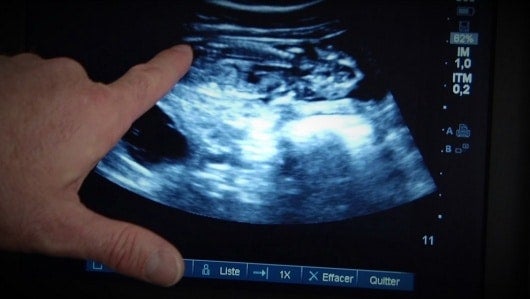

Los magistrados de la Corte deliberaron desde las 9 de la mañana de este miércoles luego de una tutela presentada por una mujer de 33 años que quiso acceder a la interrupción del embarazo desde las primeras semanas de gestación, pero que por trabas burocráticas no lo logró a pesar de que había malformación del feto.